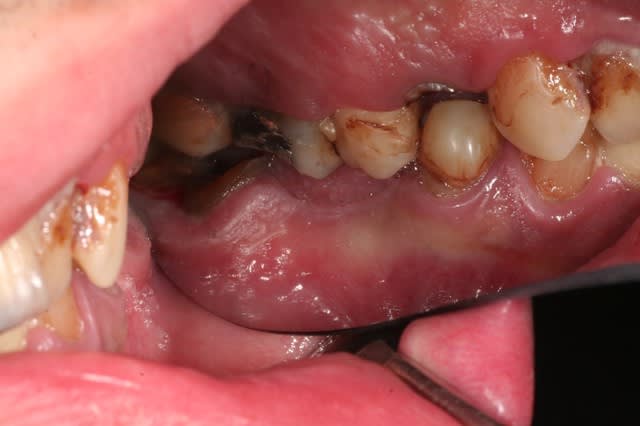

je crois que là, à part dentisterie véto et pédo, tu as tous les thèmes d'eugénol dans une seule bouche.

j'explique le contexte: jeune homme à l'adolescence plutôt difficile, rangé des voitures. s'est mis à son compte.

hyper motivé, à souscrit un crédit pour la totalité des travaux. on démarre dans quinze jours si tout va bien.

va t y sermoner sur l'hbd? grrr... avec delicatesse surement, parceque le jeune homme a visiblement passé beaucoup de temps chez les dentistes, beaucoup de séances, et le resultat...

ensuite comment la mécanique alhounienne va t elle s'epanouir et se révéler? par exemple, mais entre autre, va t y se bagarrer avec cette 34 en reprenant l'endo et en esperant resurrection (c'est jouable), va t y virer et implanter avec le reste (il y a tellement d'os si tentant)? comment l'endo qui est au plus profond de lui va t il se confronter avec l'implanto encore plus enfoui?

Au delà du problème de brossage, le résultat est probablement surtout dû à de l'héroïne en IV, donc si le mec est vraiment guéri (est-ce que c'est seulement possible ?) de son addiction, pourquoi pas ?